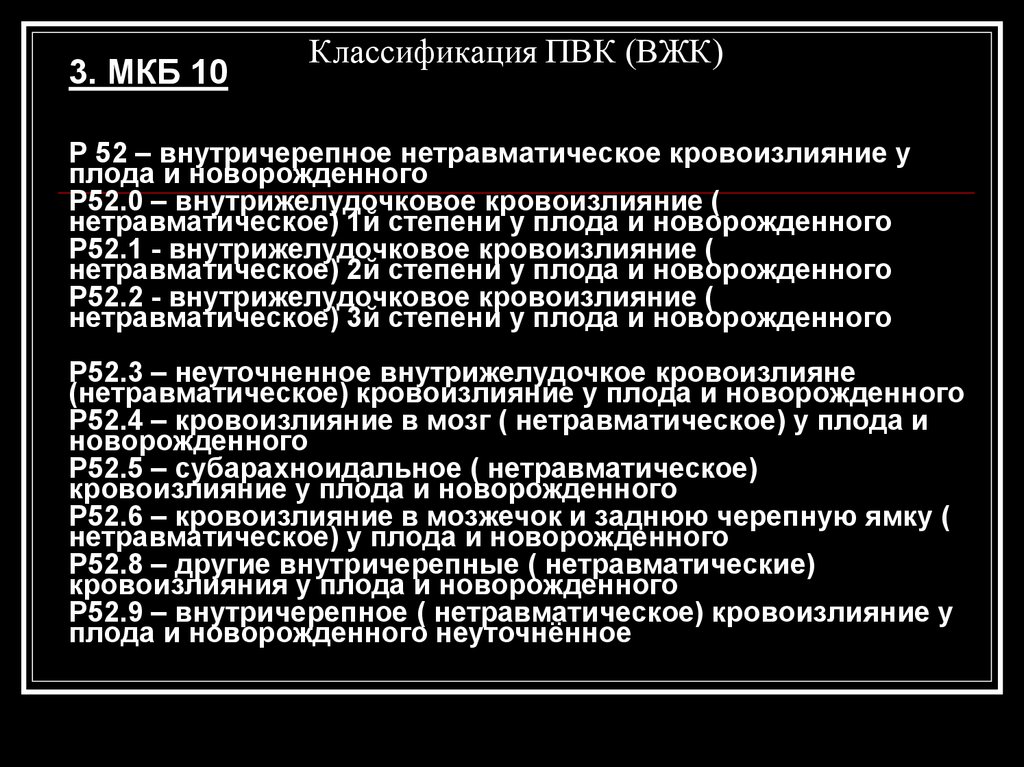

Внутричерепные кровоизлияния у новорожденных презентация - 92 фото